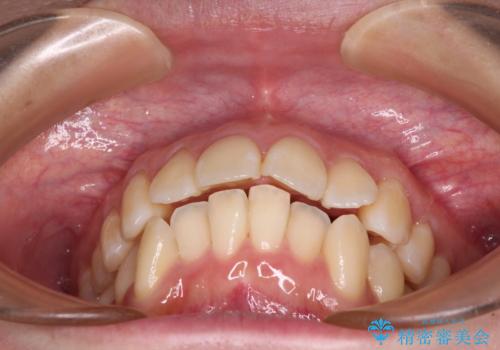

- 前歯の出っ歯と口元の閉じにくさを気にして来院された患者様です。

口元を積極的に引っ込めるために、上下左右の小臼歯4本を抜歯し、目立たないワイヤー装置にて矯正治療を行うこととしました。

上下前歯の歯軸の角度が大きく改善され、お口を閉じたときに顎先に認められた梅干し様の皺も改善されました。